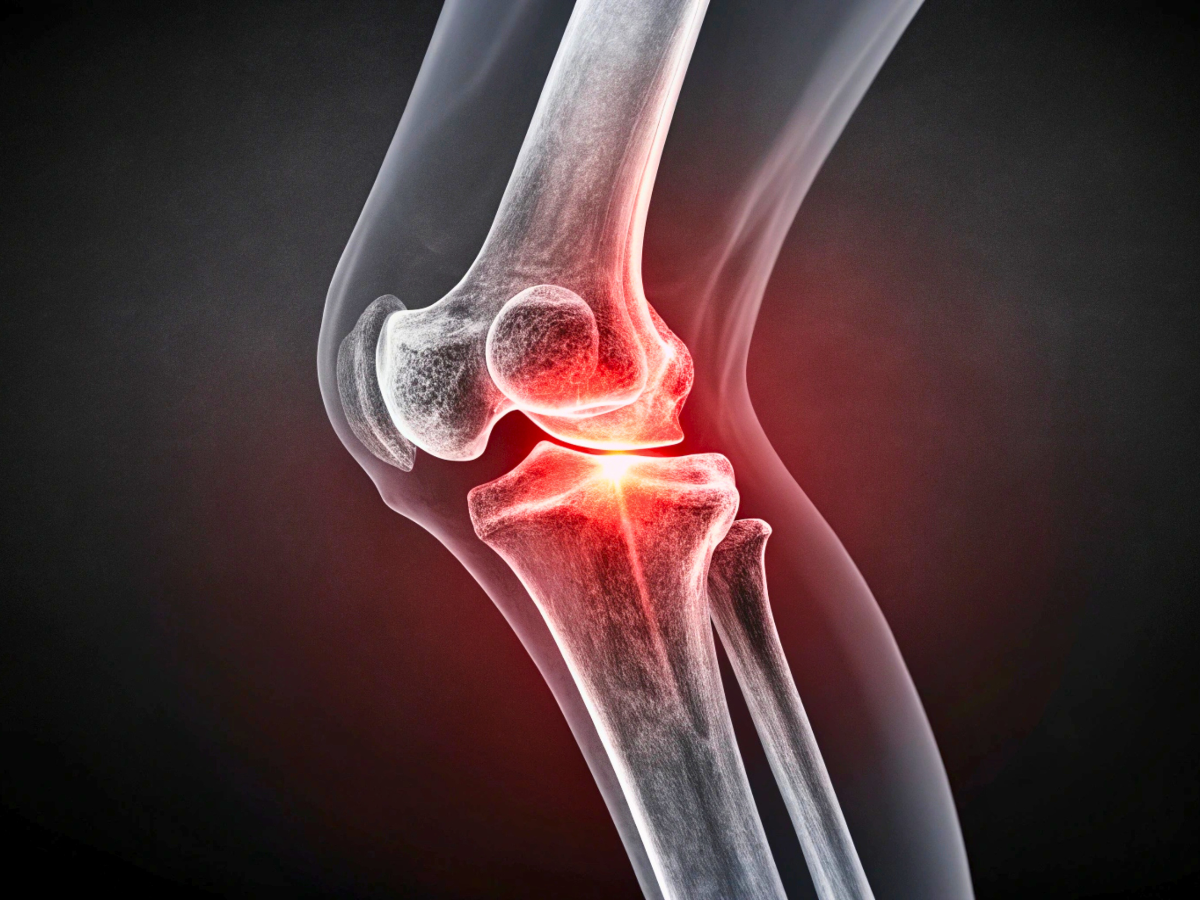

What Causes Osteoarthritis?

Osteoarthritis occurs when the cartilage that cushions and protects the bones breaks down. This cartilage normally prevents bones from rubbing against one another, but over time it can deteriorate. Contributing factors may include aging, prior injuries, or an extremely active lifestyle that places repetitive strain on joints.